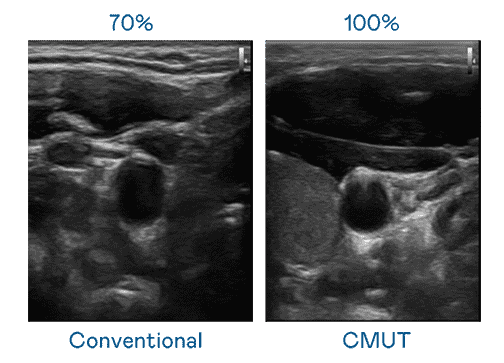

CMUT 技术是一种用电容式微机电元件来产生超音波讯号的技术。。与传统 PZT 压电式技术相比,,CMUT 频宽增加 30%,,,更宽频的超音波讯号让影像解析度大幅提升,,是实现高影像品质医疗超音波扫描、、、促进精准医疗发展的关键技术。。。

超音波影像的解析度高低,,,,首先取决于探头能发出的讯号频宽。。。。优游UB8 CMUT 可提供高清晰的超音波讯号,,,提供高频宽、、、高灵敏度、、影像纹理细节更高的超音波影像,,协助医护人员缩短影像判读时间及利用精准的医疗影像进行诊断。。。。